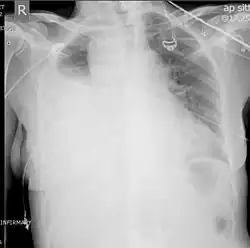

Hemothoraces are most commonly detected using a chest X-ray, although ultrasound is sometimes used in an emergency setting.[22] It can be suspected in any person with any form of chest trauma.[6] However, plain X-rays may miss smaller hemothoraces while other imaging modalities such as computed tomography (CT), or magnetic resonance imaging may be more sensitive.[22] In cases where the nature of an effusion is in doubt, a sample of fluid can be aspirated and analysed in a procedure called thoracentesis.[8] Physical examination is used initially. Auscultation has been reported to have an accuracy of nearly 100% in diagnosing hemopneumothorax.[3]

Chest X-ray

A chest X-ray is the most common technique used to diagnosis a hemothorax.[23] X-rays should ideally be taken in an upright position (an erect chest X-ray), but may be performed with the person lying on their back (supine) if an erect chest X-ray is not feasible. On an erect chest X-ray, a hemothorax is suggested by blunting of the costophrenic angle or partial or complete opacification of the affected half of the thorax. On a supine film the blood tends to layer in the pleural space, but can be appreciated as a haziness of one half of the thorax relative to the other.[5] A small hemothorax may be missed on a chest X-ray as several hundred milliliters of blood can be hidden by the diaphragm and abdominal viscera on an erect film. Supine X-rays are even less sensitive and as much as one liter of blood can be missed on a supine film.[24]

Ultrasonography may be used to detect hemothorax and other pleural effusions. This technique is of particular use in the critical care and trauma settings as it provides rapid, reliable results at the bedside.[23] Ultrasound is more sensitive than chest x-ray in detecting hemothorax.[25] Ultrasound can cause issues in people who are morbidly obese or have subcutaneous emphysema. When CT is unavailable in the current setting or the person cannot be moved to the scan, ultrasound is used.[3]

Computed tomography (CT or CAT) scans may be useful for diagnosing retained hemothorax as this form of imaging can detect much smaller amounts of fluid than a plain chest X-ray. However, CT is less used as a primary means of diagnosis within the trauma setting, as these scans require a critically ill person to be transported to a scanner, are slower, and require the subject to remain supine.[23][26]

Magnetic resonance imaging (MRI) can be used to differentiate between a hemothorax and other forms of pleural effusion, and can suggest how long the hemothorax has been present for. Fresh blood can be seen as a fluid with low T1 but high T2 signals, while blood that has been present for more than a few hours displays both low T1 and T2 signals.[27] MRI is used infrequently in the trauma setting due to the prolonged time required to perform an MRI, and the deterioration in image quality that occurs with motion.[22]